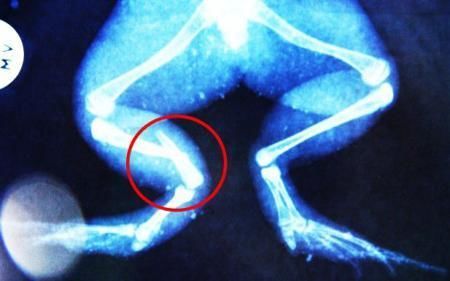

環(huán)球網(wǎng)4月2日報(bào)道 據(jù)《每日郵報(bào)》報(bào)道,上個(gè)月,南非大牛蛙布魯萊的右小腿被鄰居家的一只狗咬到,導(dǎo)致粉碎性骨折,現(xiàn)在經(jīng)過2個(gè)小時(shí)的手術(shù),它的斷腿已經(jīng)被接上,它也因此成為有史以來第一只通過外科手術(shù)用鋼針接上斷腿的青蛙。

野生生物專家安妮經(jīng)常為學(xué)校寫教材,她認(rèn)為這是人類第一次通過手術(shù)給一只青蛙接斷腿。在手術(shù)開始階段,獸醫(yī)把少量給狗用的麻醉藥注入到這只青蛙體內(nèi),讓它失去知覺。然后他在布魯萊的斷腿上切開一個(gè)小口,把一根小鋼針植入腿里。最后獸醫(yī)給它縫了9針,把切口縫合在一起。僅僅幾周后,布魯萊就能在安妮家附近活動(dòng)了。這只青蛙大約已有25歲,主要以嚙齒動(dòng)物、蛇和其他青蛙為食。布魯萊所屬的牛蛙種群正在不斷減小,目前只能在非洲南部的濕地里才能看到這種青蛙。